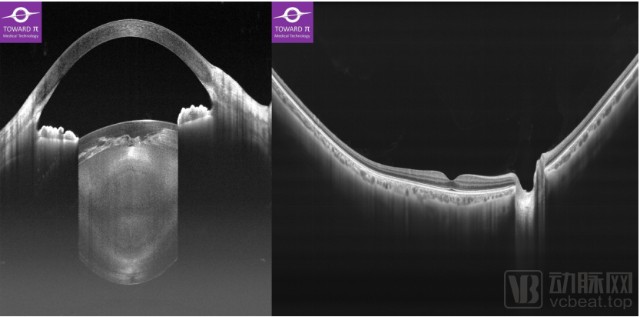

“瑶光星”是图湃医疗的主流级OCT产品,不同于“北溟鲲”的超高性能,“瑶光星”则是主打“一台OCT,满足所有临床诊断需求”的“全景前后节一体”功能。“瑶光星”具备10万次扫描速度,而成像深度则达到14mm,这也是目前为止眼科OCT领域的最大成像深度。该深度使得“瑶光星”不仅能用于后节断层和血流成像,还可以进行优异的全景前节成像,其前节成像功能甚至强于昂贵的专用前节OCT设备。因此,“瑶光星”也成为了目前全球唯一一款“全景前后节一体式”的多功能、高性能OCT产品,受到二三级医院、民营医院用户的青睐。

眼科医疗设备有哪些【首发】图湃医疗今年再获2亿元B轮融资,引领国产眼科设备崛起_https://www.jmylbn.com_新闻资讯_第4张 “瑶光星”拍摄的全景前后节一体式OCT断层影像  企业供图